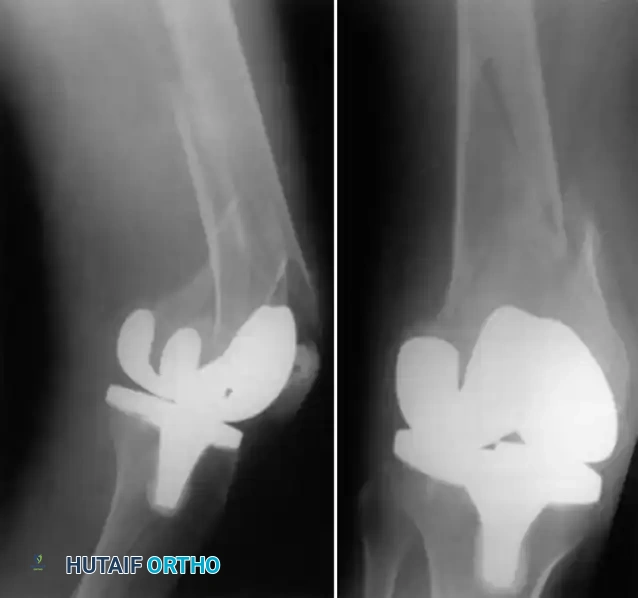

Two-Stage Revision Arthroplasty

The gold standard for chronic PJI.

* Stage 1: Explantation of components, radical debridement, and placement of an antibiotic-impregnated cement spacer.

* Stage 2: After 6-8 weeks of IV antibiotics and normalization of inflammatory markers, the spacer is removed, and revision components are implanted.

Complex two-stage revision TKA utilizing diaphyseal engaging stems and metaphyseal augments to manage severe bone loss.